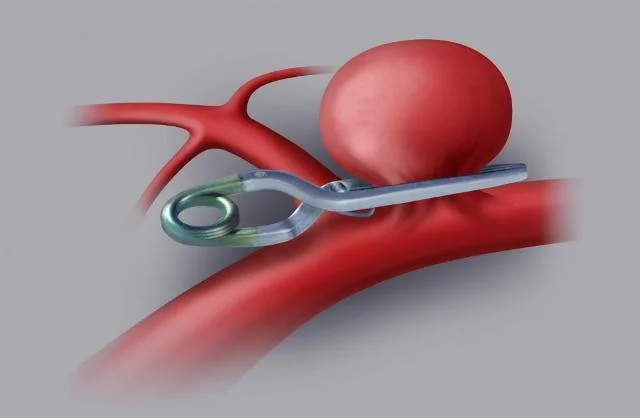

Cirurgia aberta

Apesar de ser um método invasivo, em algumas situações, a cirurgia pode ser a melhor opção.

Nesse caso, o médico coloca um pequeno clipe na entrada do aneurisma para impedir a passagem do sangue para dentro da “bolha”.

Esse tipo de cirurgia é indicada apenas em casos específicos, quando os benefícios superam os riscos.